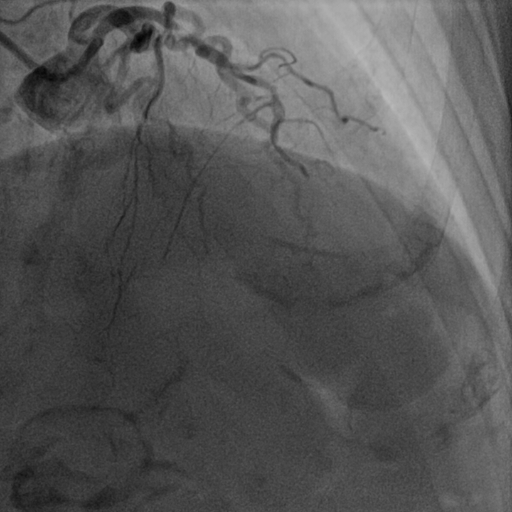

前降支介入术前图像

在经过充分的抗心衰治疗后,徐奶奶在大家的鼓励下上了手术台。冠状动脉造影显示三支冠状动脉严重狭窄,前降支(LAD)近段狭窄99%,回旋支(LCX)远端狭窄80%,右冠状动脉(RCA)中远段弥漫狭窄90%。